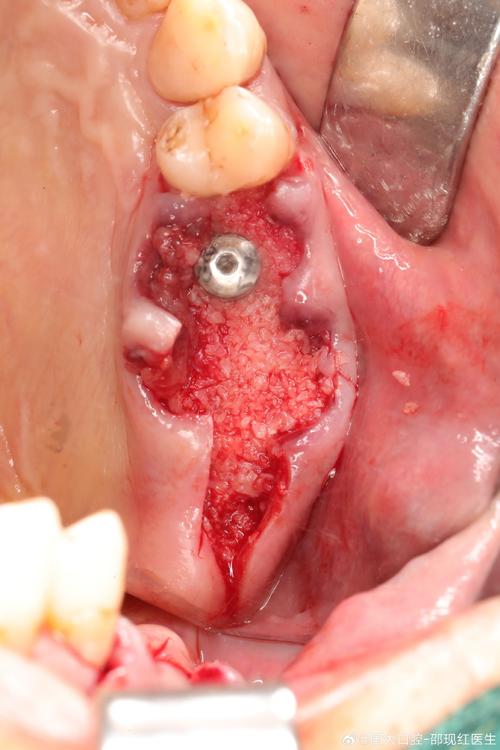

- 即刻手术:局部麻醉下拔除患牙,同期将种植体(如钛合金材质)植入牙槽骨,通过基台连接临时牙冠,即刻恢复牙齿形态;